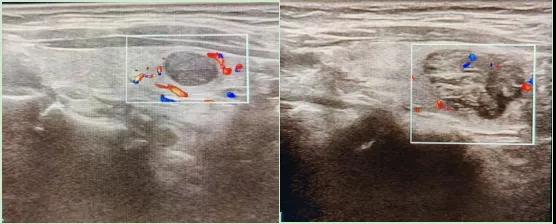

彩色血流顯示:用紅藍色標(biāo)記血流信號,區(qū)分腫瘤的供血情況。

1.形態(tài):良性多呈圓形,邊界清晰;惡性可能不規(guī)則、邊緣模糊。

2.回聲:低回聲結(jié)節(jié)風(fēng)險較高(像“烏云”一樣暗)。

3.鈣化:細(xì)小砂礫樣鈣化提示惡性可能。

4.血流信號:惡性結(jié)節(jié)常有豐富紊亂的血流。